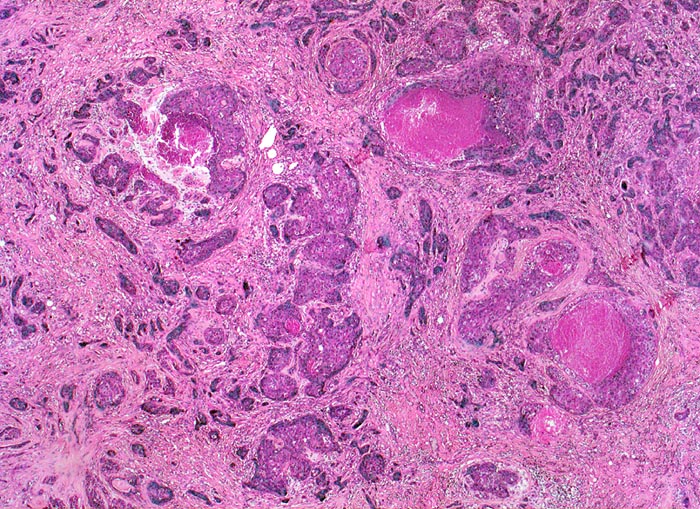

wenig differenziertes invasives duktales Mammakarzinom

Das Karzinom bildet keine drüsigen Strukturen, sondern ausschliesslich solide Zellstränge mit infiltrativem Wachstum in desmoplastischem Stroma. Fokal sind Tumornekrosen erkennbar.

Das histologische Grading (G1 bis G3) der Mammakarzinome wird bestimmt aufgrund des Prozentualen Anteils von drüsigen und soliden Tumorarealen, der zytologischen Atypien und der Anzahl Mitosen. Diesen drei Komponenten wird ein Wert zwischen 1-3 zugeordnet und zu einem Score aufaddiert (B.R.E. Score).

Score 3-5=G1

Score 6-7=G2

Score 8-9=G3

Der vorliegende Tumor hat einen hohen Anteil solider Tumorareale, zeigt ausgeprägte Zellatypien und zahlreiche Mitosen entsprechend einem wenig differenzierten Karzinom.